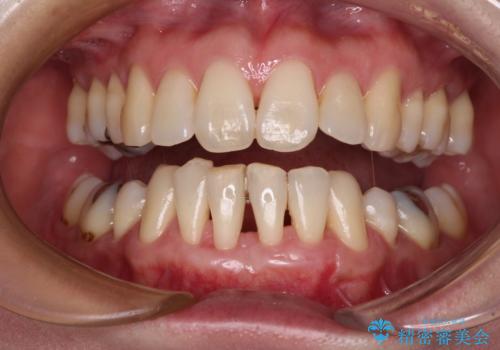

- 矯正治療により下の前歯の歯肉が退縮してしまい、根が見えていることが気になるとのことで来院された患者様です。

歯肉退縮に対して、上顎からの結合組織移植術(CTG)により、歯根の被覆を行うとともに、歯肉の厚みを増すことで将来の退縮リスクを抑制することとしました。

歯と歯と歯肉の間にある三角形の隙間(ブラックトライアングル)は歯肉移植では改善できないため、根面被覆できる量に限界がありましたが、最大限回復させることができました。